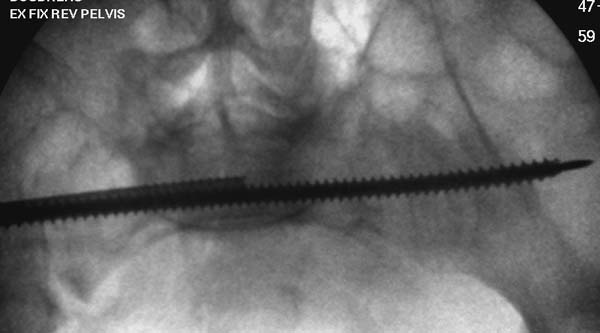

Большое спасибо всем Вам за помощь! Вчера прооперировали пациентку. Выполнили закрытую репозицию левой половины таза на тракционном столе под контролем ЭОП, закрытая фиксация левого КПС двумя каннулированными винтами. Учитывая удовлетворительное стояние отломков лонной и седалищной костей справа, а так же удовлетворительную ширину лона передние отделы стабилизировали системой ЦИТО

Послеоперационные КТ прилагаются

Винты введены в S1